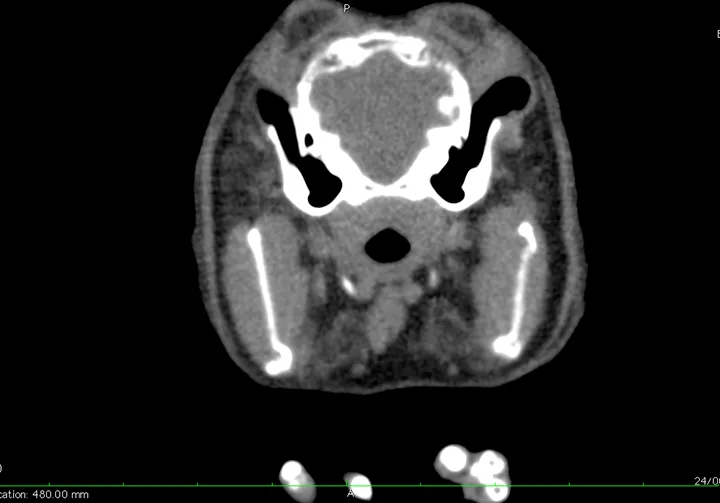

Snowball was quiet, alert, and responsive, demonstrating a right-sided head tilt of ≈30 degrees that worsened with manipulation and movement (Figure 1). Horizontal nystagmus with fast phase to the left was present intermittently. He was able to walk and hop with relative normalcy at slow speeds but stumbled and fell with a more rapid gait. Heart and respiratory rates were within normal limits. Gut sounds were reduced bilaterally. External ear canals appeared normal.

A rabbit with head tilt